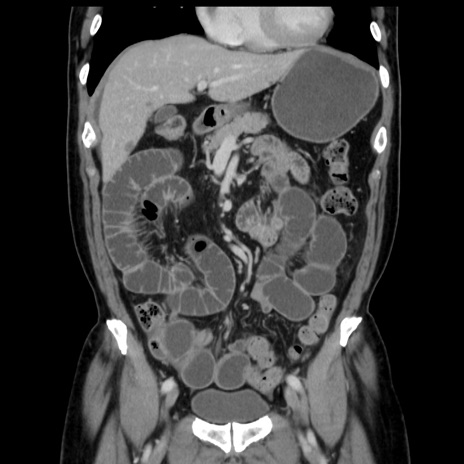

症例16(冠状断像)

【症例】 70歳代男性

【主訴】 腹痛、嘔吐

【現病歴】 約1ヶ月前より間欠的に腹痛と嘔吐あり、当院消化器内科を受診したところCTで多発する肝臓のLDAを指摘され、精査中であった。以降は消化器症状は安定していたが、2日前より嘔気と腹痛があり、同日より排便・排ガスが消失した。改善認めず、 本日、救急外来を受診した。

【既往歴】 大腸ポリープ切除後。

【身体所見】意識清明・会話良好、BT 36.3℃、BP 127/80mmHg、 P 80bpm、腹部:膨満あり、平坦・軟、上腹部正中および下腹部正中に圧痛あり、反跳痛なし、筋性防御なし。

【データ】WBC 7200、CRP 0.77